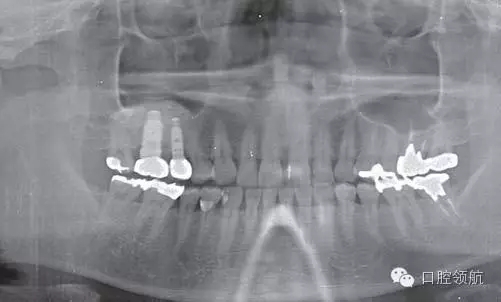

患者10年前,在外院于( 左上第六顆牙)區(qū)行上頜竇底提升術(shù)同期植入種植體,經(jīng)過10年上頜竇內(nèi)生成骨完全吸收消失了(圖1)?;颊叽舜蝸碓菏且?yàn)猷徰? 左上第五顆牙) 不能保存,希望行種植修復(fù)治療。

圖1 術(shù)前牙片。由于上頜竇底黏膜提升植骨術(shù)而在上頜竇內(nèi)生成的骨已完全消失。